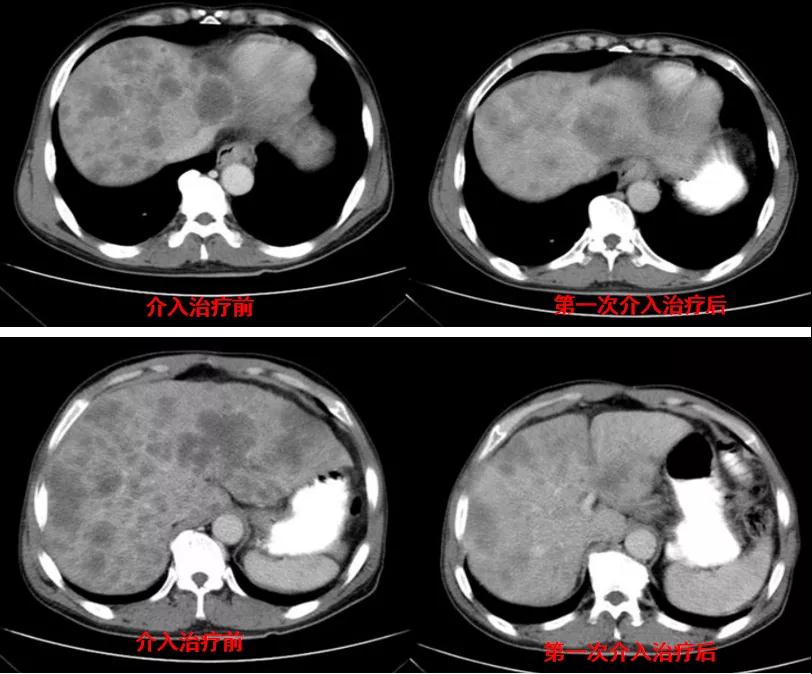

诊治经过:2021年5月16日患者行第三次经皮动脉化疗灌注栓塞术(铂类+氟尿嘧啶)治疗,并继续联合吡咯替尼治疗。结果见图4。

图4

总结:本例患者为胃癌IV期,伴肝转移及淋巴结转移,经介入联合吡咯替尼治疗后,肝转移灶显著缩小。治疗前肿瘤标志为:癌胚抗原3574.3ng/ml、CA12-5 650U/ml、CA19-9 1212U/ml、CA15-3 333U/ml;治疗后肿瘤标志为:癌胚抗原7.6ng/ml、CA12-5 12.8U/ml、CA19-9 17.4U/ml、CA15-3 6.7U/ml。治疗后,肿瘤标志物显著降低,且腹部CT结果显示该患者肝转移病灶较治疗前明显减少。患者目前带瘤总生存达10个月,病情稳定。